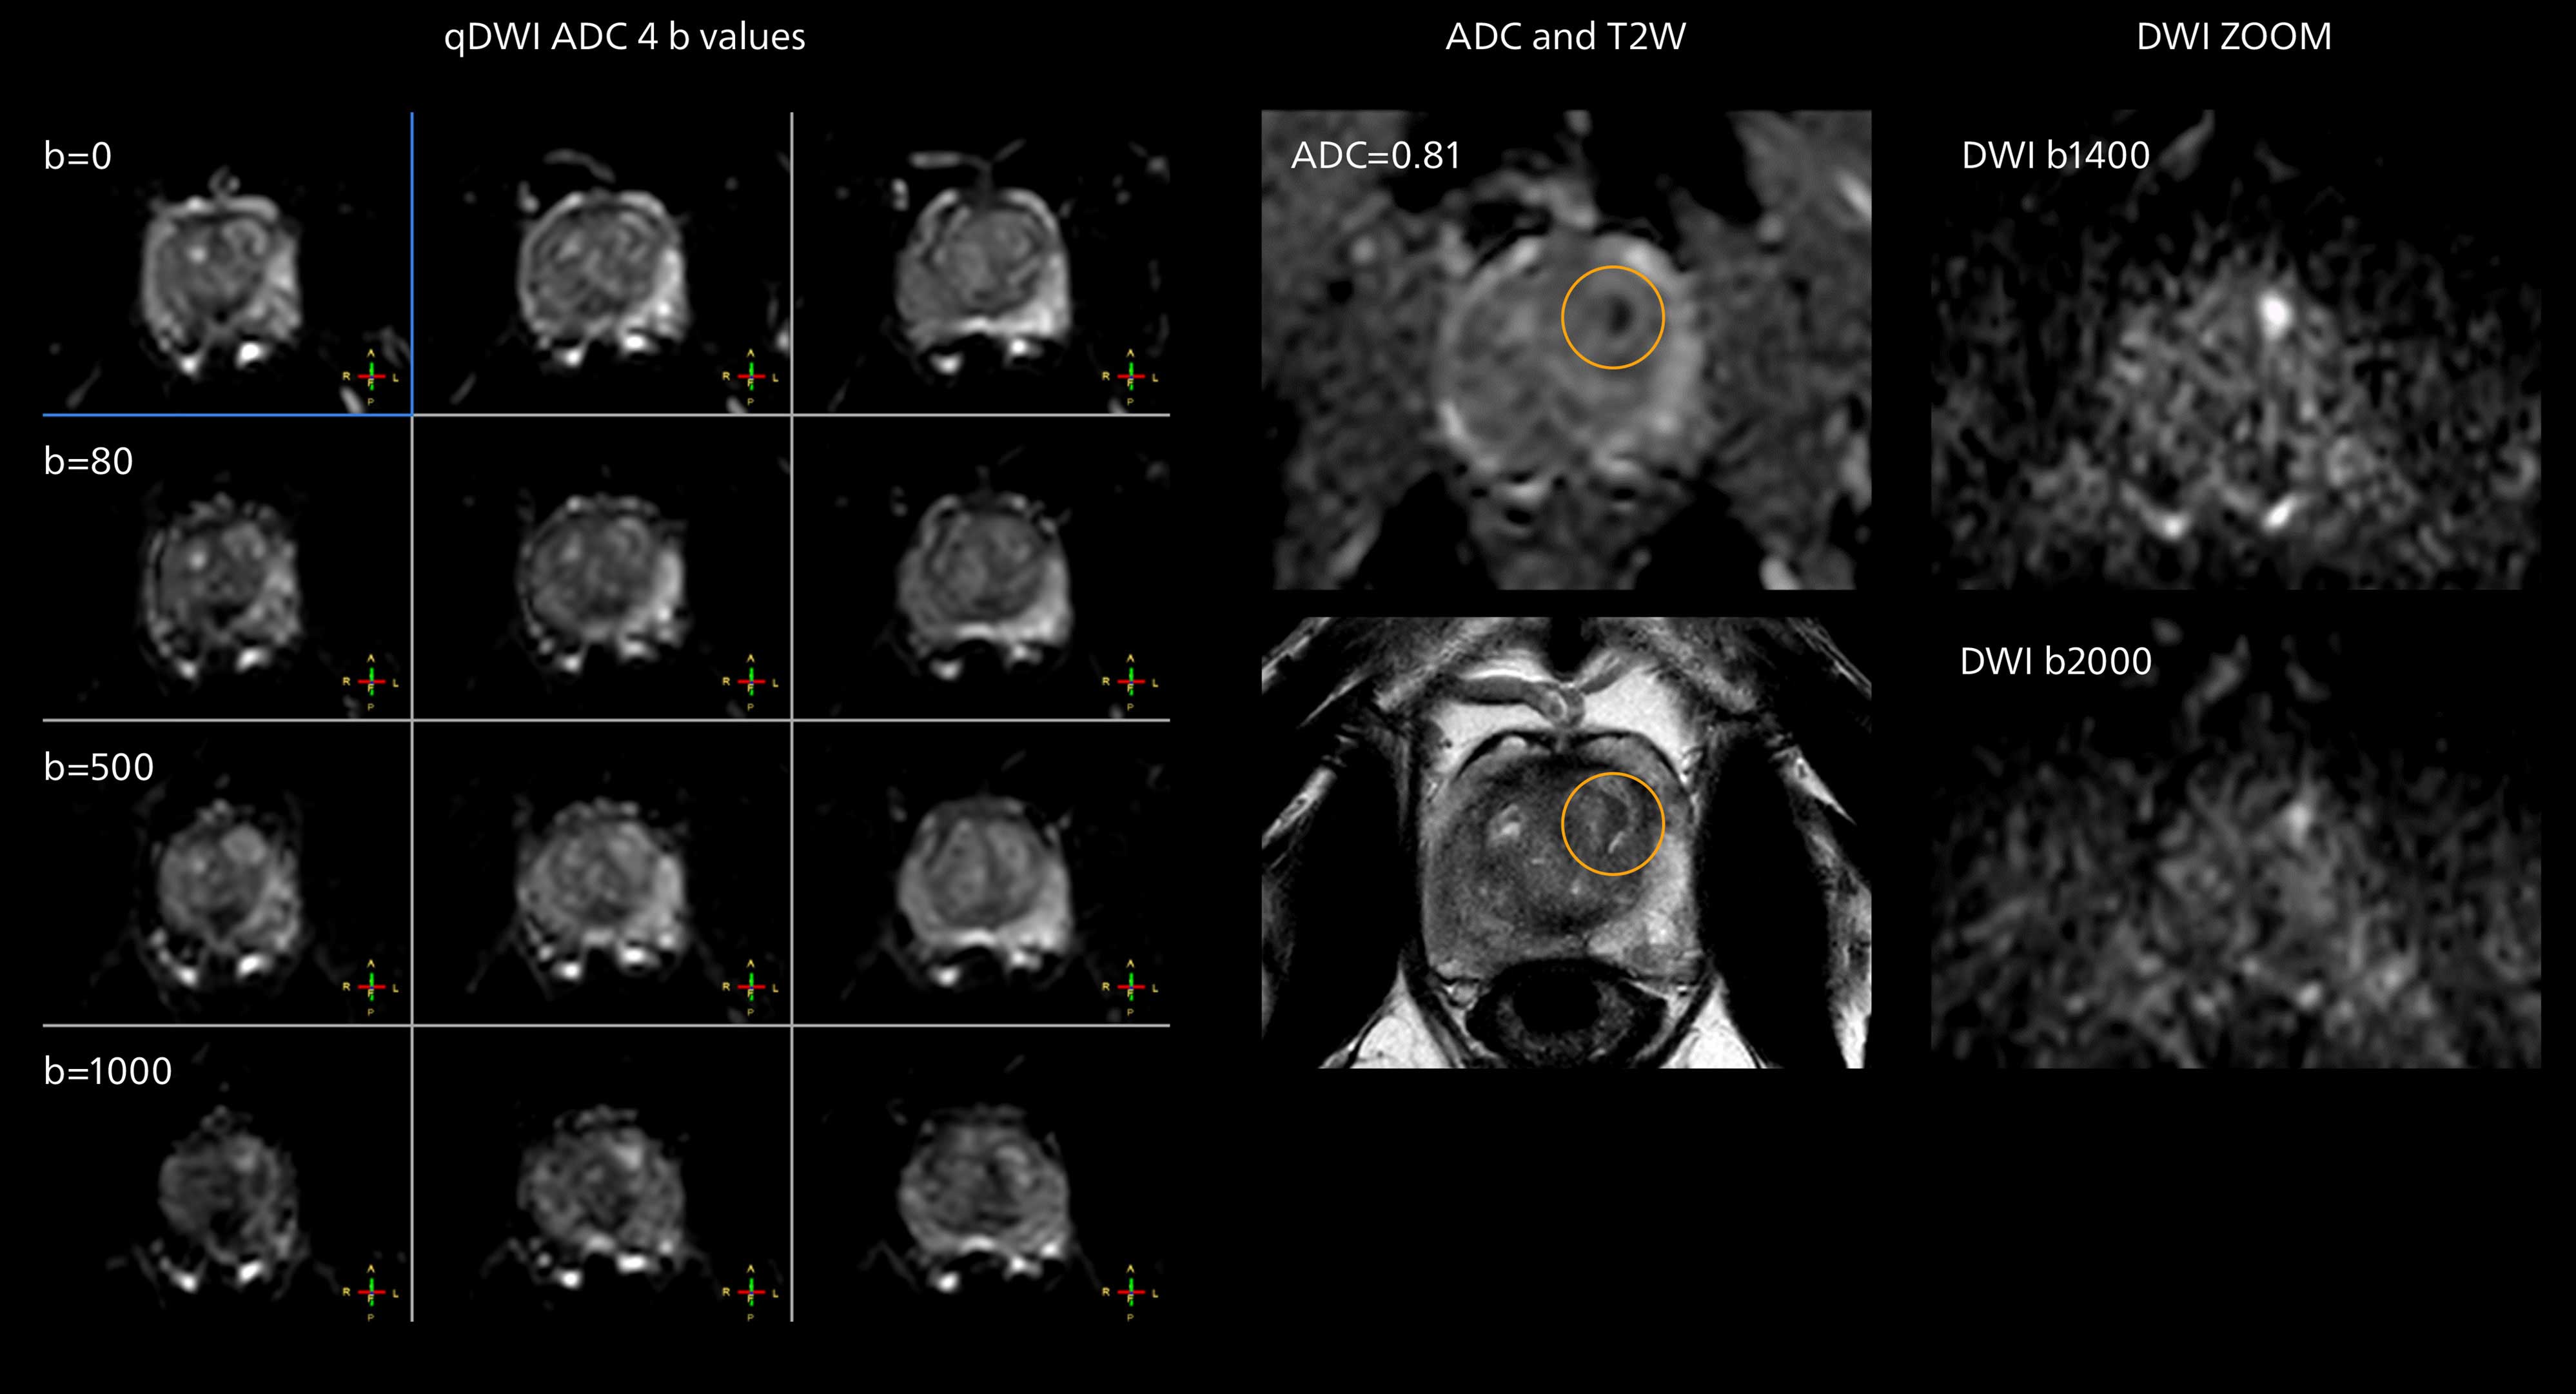

Diffusion weighted imaging of prostate

The examples on the left show the regular clinical diffusion protocol with four b-values up to b1000 s/mm². On the right, the T2W image shows a hypointense lesion that has low ADC and is clearly visible in b1400 and b2000 diffusion images, suggesting malignancy.

Diffusion weighted imaging of prostate

The examples on the left show the regular clinical diffusion protocol with four b-values up to b1000 s/mm². On the right, the T2W image shows a hypointense lesion that has low ADC and is clearly visible in b1400 and b2000 diffusion images, suggesting malignancy.